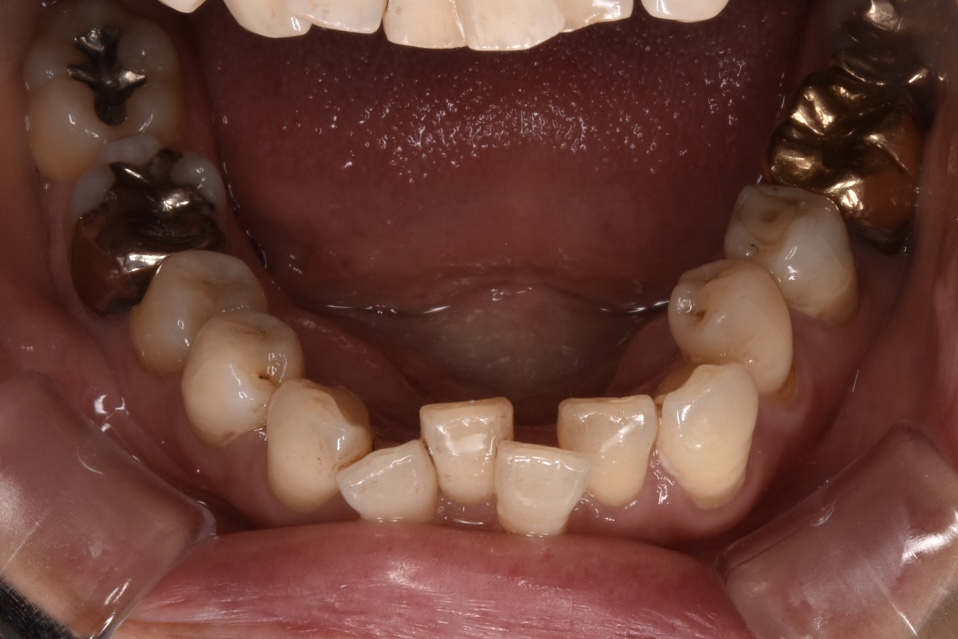

矯正前

前歯を中心に叢生(ガタガタ歯並び)がみられます。

矯正前の横顔や正面、咬合面の写真です。